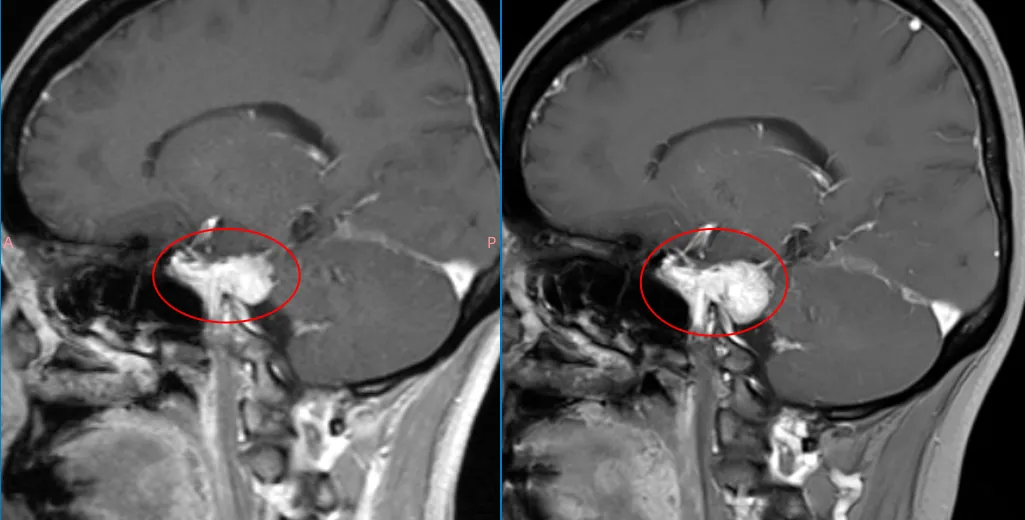

当他找到福教授时,脑膜瘤已经延伸到Meckel's囊。Meckel's囊内侧为颈内动脉海绵前段,前方为海绵窦,包含三叉神经分支(V₁、V₂)及动眼神经、滑车神经。

“手术是可行的,而且我认为是必要的。是否应尽早手术,要看核磁对比,肿瘤是否增大?若肿瘤已有增长,则没有理由继续观察,因为手术会变得更加困难,并增加三叉神经损伤风险。”

当对比核磁后,福教授发现脑膜瘤有明显生长,影像学证实目前已具备手术指征。